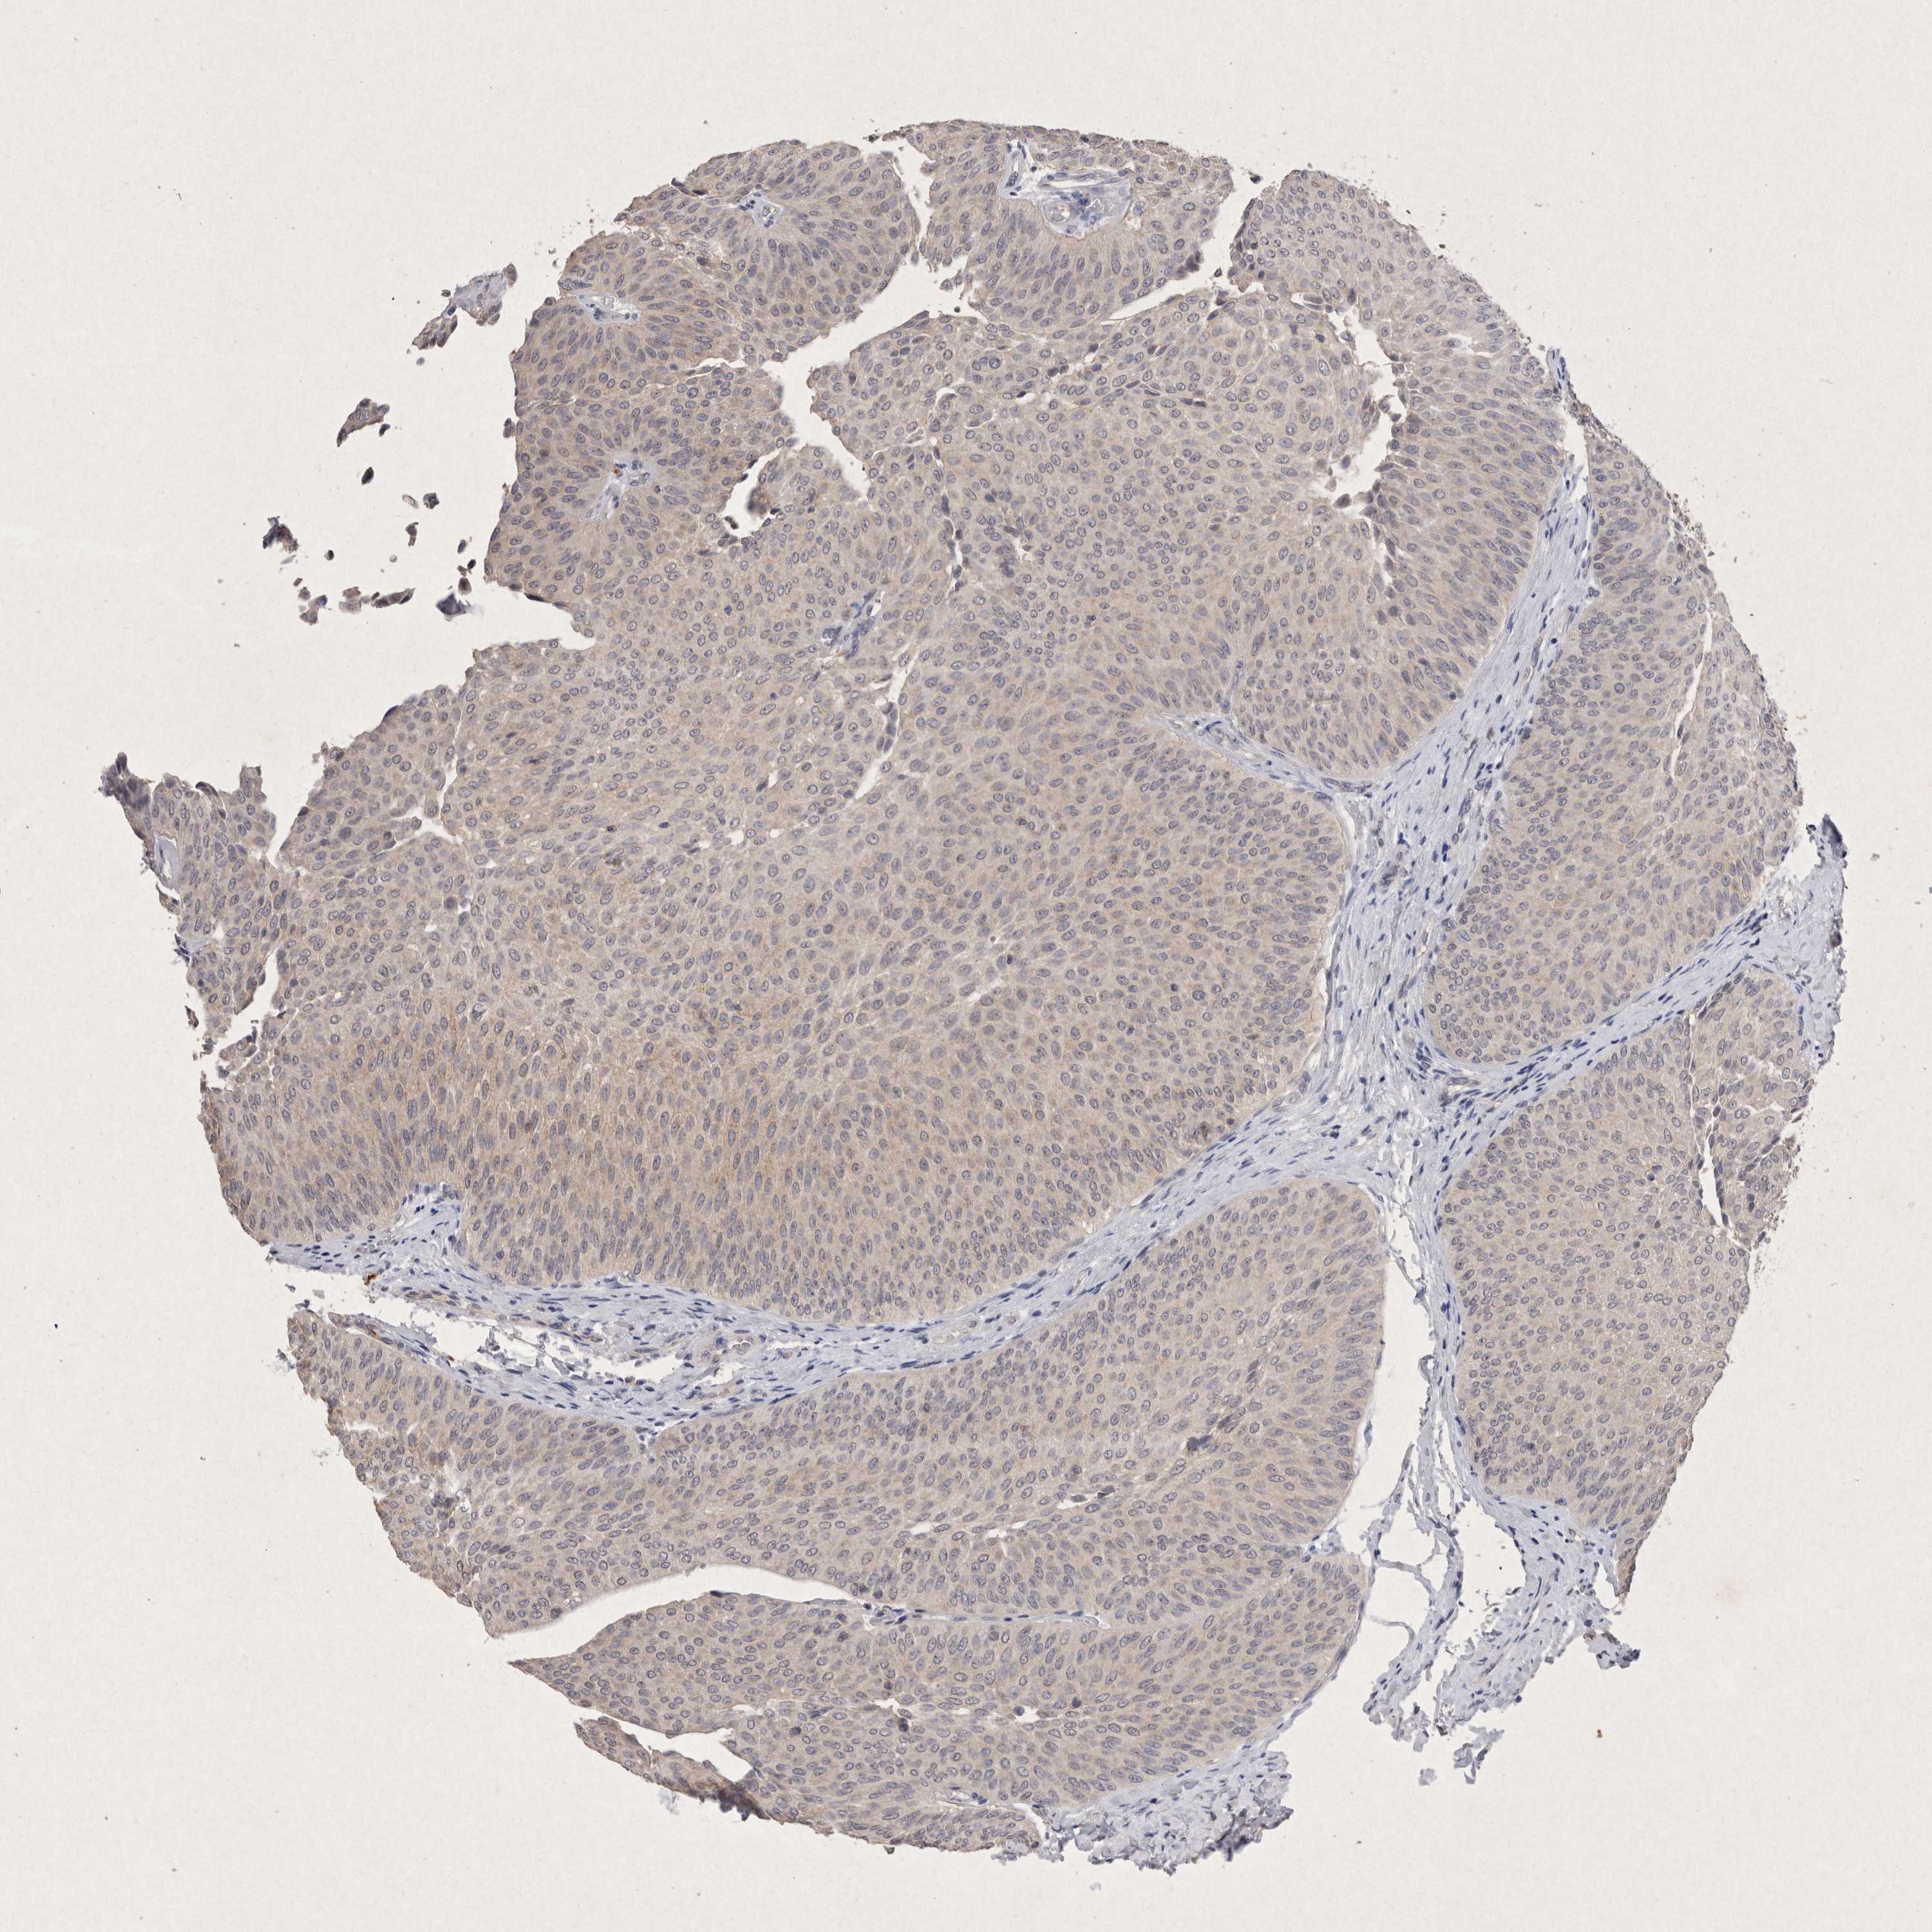

UROTHELIAL CANCER - Protein expressioni

A mouse-over function shows sample information and annotation data. Click on an image to view it in a full screen mode. Samples can be filtered based on level of antibody staining by selecting one or several of the following categories: high, medium, low and not detected. The assay and annotation is described here.

Note that samples used for immunohistochemistry by the Human Protein Atlas do not correspond to samples in the TCGA dataset.

Antibody stainingi

Antibody staining in the annotated cell types in the current human tissue is reported as not detected, low, medium, or high, based on conventional immunohistochemistry profiling in selected tissues. This score is based on the combination of the staining intensity and fraction of stained cells.

Each image is clickable and will lead to virtual microscopy that enables deeper exploration of all samples and also displays staining intensity scores, fraction scores and subcellular localization as well as patient and tissue information for each sample.

Antibody HPA038469

Antibody CAB022664

Antibody CAB034035

Staining

High

Medium

Low

Not detected

Intensity

Strong

Moderate

Weak

Negative

Quantity

>75%

75%-25%

<25%

None

Location

Nuclear

Cytoplasmic/membranous

Cytoplasmic/membranous,nuclear

Urothelial carcinoma, High grade

Urothelial carcinoma, Low grade